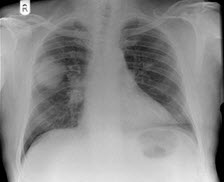

女性,51岁,胸痛数月,痰血2天,X线检查见图,最可能的诊断是()

A.左肺癌

B.左侧炎性假瘤

C.左侧纵隔肿瘤

D.左肺转移瘤

E.支气管扩张